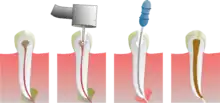

Le traitement endodontique consiste à :

- éliminer ce qui reste de tissus vivants infectés ou potentiellement infectés à l'intérieur de la dent (pulpe dentaire)

- bien nettoyer l'intérieur de cette dent, par une action mécanique : grattage de la surface intérieure des canaux pulpaires (à l'aide de limes endodontiques manuelles ou mécaniques), associée à une action chimique : irrigation avec de l'hypochlorite de sodium (eau de Javel diluée à 3 %), qui est le désinfectant le plus efficace.

- mettre en forme la lumière canalaire jusqu'au foramen apical, à l'aide de limes manuelles ou de limes mécanisées afin que la solution d'irrigation pénètre partout.

- sécher le système canalaire

- réaliser l'obturation canalaire, le plus souvent à l'aide de gutta-percha chauffée ou froide, liée aux parois dentinaires avec un ciment canalaire (le plus souvent un mélange d'oxyde de zinc et d'idothymol, appelé pâtes de Roy).

Pour cela le dentiste réalise généralement une anesthésie locale, pour que le geste ne soit pas douloureux (la dent, même partiellement nécrosée, restant généralement sensible). Une ouverture adéquate est réalisée au niveau de la face occlusale de la dent, pour accéder à la pulpe camérale et radiculaire.

Ensuite il faudra reconstituer la dent, soit avec une obturation coronaire si cette dent n'est pas trop délabrée, soit par une reconstitution prothétique (couronne) si elle est trop délabrée, afin d'assurer l'étanchéité du traitement et éviter que la racine ne soit recolonisée par les bactéries.